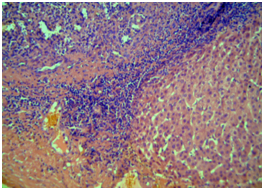

Male, 47 years old, with an incidental finding of hepatic lesion, during investigation of nephrolithiasis. Previous history of splenectomy after abdominal trauma due to automobile accident 20 years ago. Hypertensive in use Olmesartan, denied other pathologies and surgeries. On physical examination: good general condition, anicteric, painless abdomen, without palpable masses. Laboratory tests: Hb 14g/dL (13,5 - 17,5), Hct 44,4% (39 - 55), Platelets 268,000/mm3 (150.000 - 400.000), creatine 0,9mg/dL (1,5), INR 0,8, CEA 1,33 ng/mL (<3,0), CA 19-9 20U/mL (<37), AFP 1,5ng/dl (<7,22 ), albumin 4,19g/dL (3,4 – 4,8), AST 20U/L (17 - 55), ALT 18U/L (21-71), GGT 54U/L (15/73), AP 48U/L (38 - 126), total bilirrubin 0,57mg/dL (0,2 – 1,3). MRI showed nodular hepatic lesion, 42x41x28mm, slight hyperintense in T2, with contrast enhancement and washout in late phase, in segment II, without dilatation of biliary tract (Figures 2). The initial diagnosis was hepatic adenoma. Proceeded with hepatic segmentectomy, with good evolution. The surgical specimen referred to pathological anatomy and revealed hepatic splenosis (Figures 1).

Intrahepatic splenosis shows increased enhancement on CT or MR images during the arterial phase. Performing gadoxetic acid–enhanced hepatocyte-phase MR imaging does not help because intrahepatic splenosis is hypointense during the hepatospecific phase. The MR technique involving administration of small iron oxide particles (SPIO-Endorem), which is taken up by liver and spleen reticuloendothelial cells, has proven to be effective in differentiating intra-hepatic splenosis from other lesions.14,15,18 With SPIO (superparamagnetic iron oxide) intrahepatic splenic nodes remain hyperintense.19 Noncontrast CT reveals a well circumscribed iso- or hypodense mass in the liver, while noncontrast MRI demonstrates mild-to-moderate hyperintensity on T2-weighted image and hypointensity on the T1-weighted image. A dynamic study on CT and MRI shows a slight to intense enhancement, which may be homogeneous or heterogeneous during the arterial phase but enhancement is diversely during the portal venous and equilibrium phases in different cases. Compared with the surrounding hepatic parenchyma, the lesion could reveal hypodensity and hypointensity, or hyperdensity in the arterial phase. Or it can demonstrate diminished enhancement, slight enhancement, or increased enhancement during the following phases (Figure 2 & 3).19,20

Figure 2 Magnetic Resonance Imaging (MRI). T2-weighted (A and B) and T1-post-contrast (C, D and E) images, in axial (A, C, D and E) and coronal (B) planes, that demonstrate subcapsular nodule in liver segment II, with intermediate sign in T2, enhancement in the post-contrast arterial phase (C) and washout with capsular enhancement in the venous phase (D). Signs of splenectomy and small implants of splenic tissue in the left subphrenic region (E) are also noted.